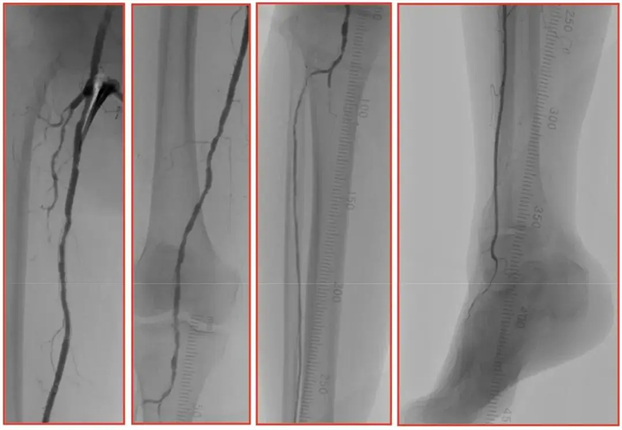

术前造影

造影示血管重度钙化影,右股浅、腘动脉多发节段性重度狭窄,膝下胫前动脉起始段重度狭窄,胫腓干、腓、胫后动脉全程闭塞,右足背动脉显影浅淡、足底内外侧动脉脉未见主干显影。